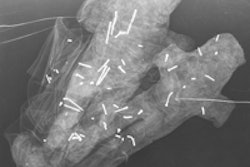

Articles in the latest issue (BJR, April 2014, Vol. 87:1036) include overviews of topics such as postmortem MRI as an alternative for nonforensic autopsy in fetuses and children, adult postmortem imaging in traumatic and cardiorespiratory death and its relation to clinical radiological imaging, and advances in postmortem CT angiography. An original article from Swiss authors focuses on identifying methamphetamine drug mules using digital radiography.